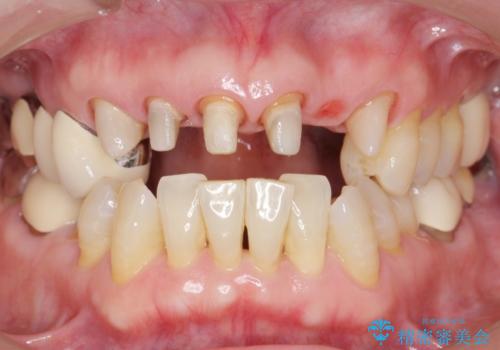

- 20年前に美容外科クリニックで治療した前歯をやりかえたいとのご希望で来院されました。

上の前歯6本はメタルボンドクラウン(内側が金属の被せ物)で補綴されており、顕著な歯肉退縮を認めました。

被せ物を除去したところ根管治療後の処置が不十分であったため、ファイバーコア(金属を用いない強くてしなやか材質の土台)を植立したのち、ジルコニアセラミッククラウンによる治療を行いました。